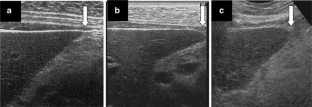

Fig. 1